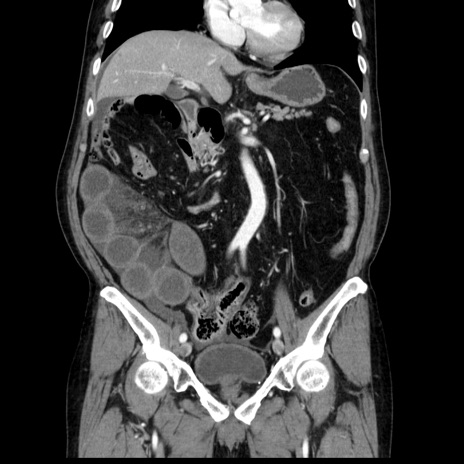

症例30(冠状断像)

【症例】80歳代男性

【主訴】臍周囲痛

【現病歴】約6時間前から臍下部痛が出現。次第に腹部膨隆・背部痛も生じてきたため来院。背部痛の場所は変化しない。

【既往歴】腎盂腎炎

【身体所見】意識清明、BT 36.3℃、BP  131/87mmHg、P 87bpm、SpO2 100%(RA)、臍周囲自発痛・圧痛あり、反跳痛なし、自発痛部位に一致して板状硬あり、腹部膨隆、腸雑音減弱、CVA tenderness両側陰性。

【データ】WBC 19600、CRP 0.33